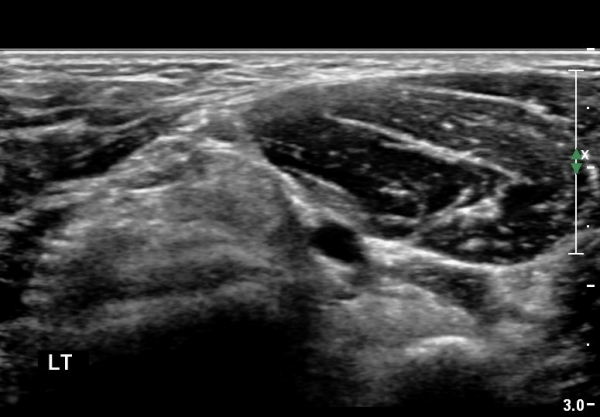

¿ìÃø ÆÈ²ÞÄ¡ ¾ÕÂÊ¿¡¼­ ÀÌµÎ¹Ú±Ù°Ç È¾´Ü¸é°Ë»ç¿¡¼­ À̵ιڱٰǿ¡ ƯÀÌ ¼Ò°ßÀ» º¸ÀÌÁö ¾Ê(±×¸² 1, 2).